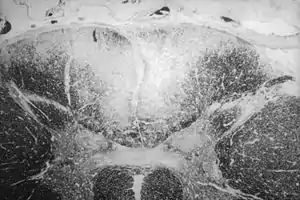

| Axial section of the spinal cord showing syphilitic destruction (whitened area, upper center) of the posterior columns which carry sensory information from the body to the brain | |